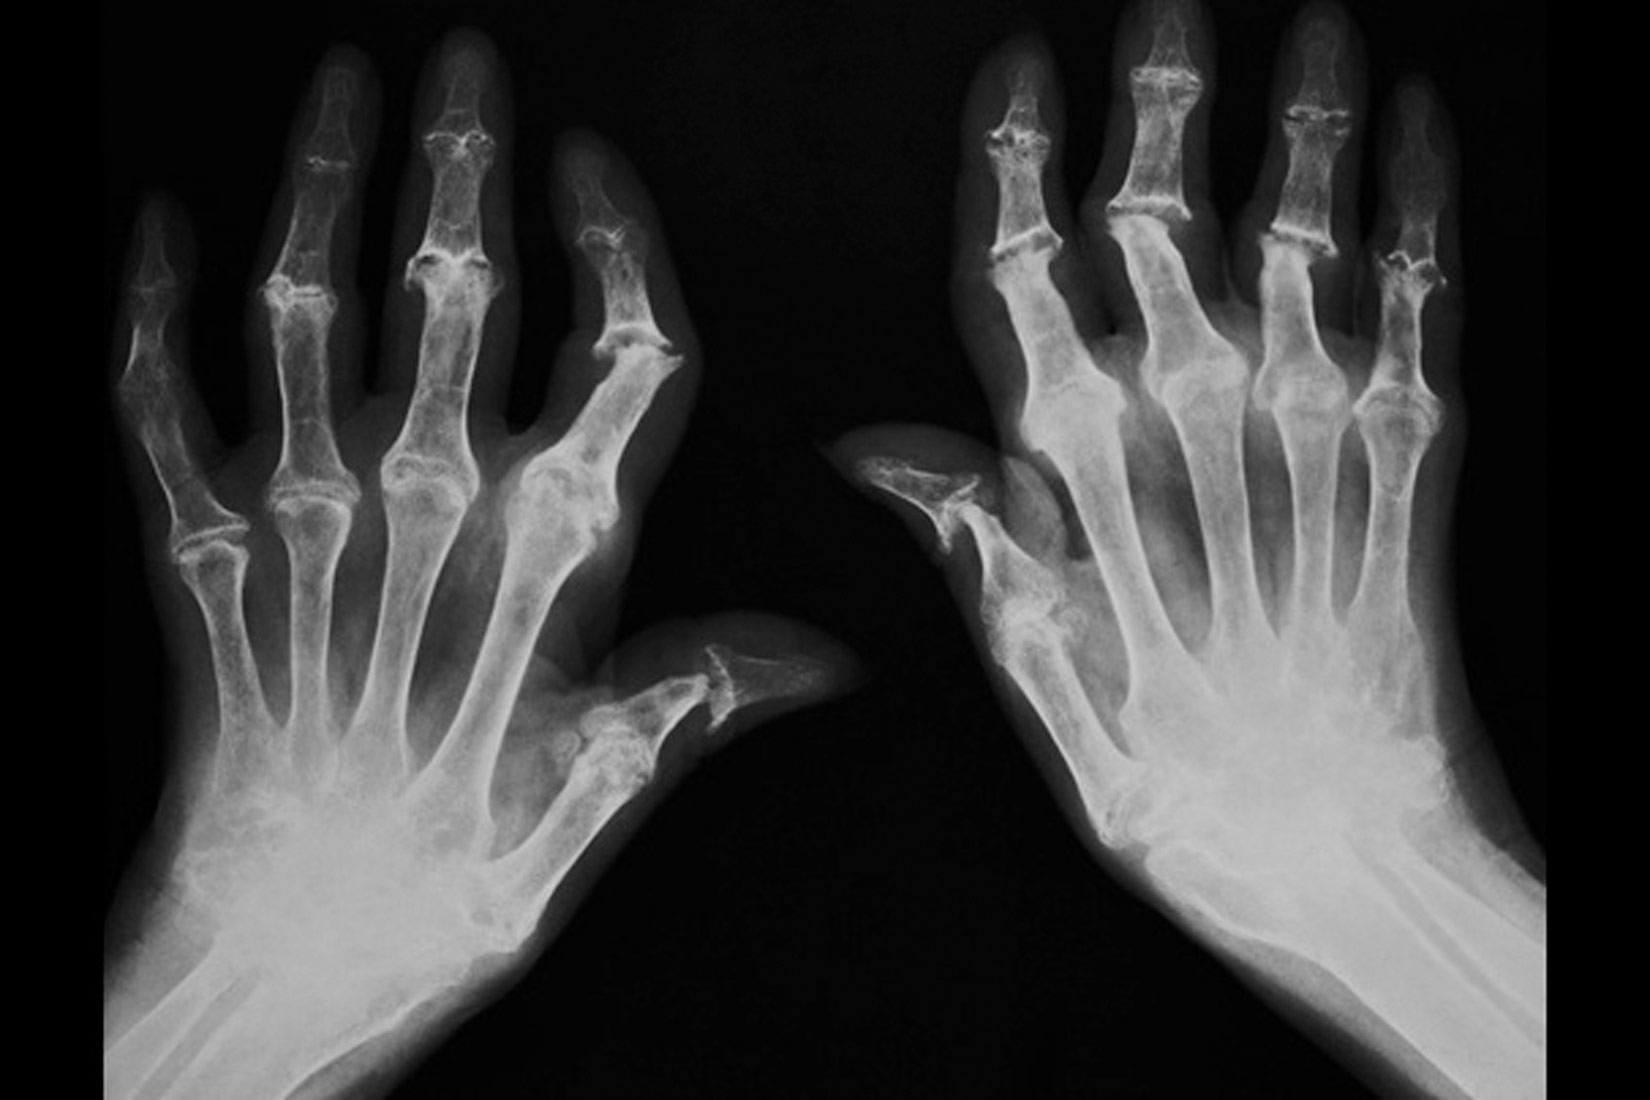

Artritis

Stanje pri kojemu dolazi do trošenja zglobne hrskavice naziva se

On se češće javlja kod osoba u starijoj životnoj dobi.

Artritis se može prepoznati po natečenim, deformiranim zglobovima čiji su pokreti bolni i ograničeni.